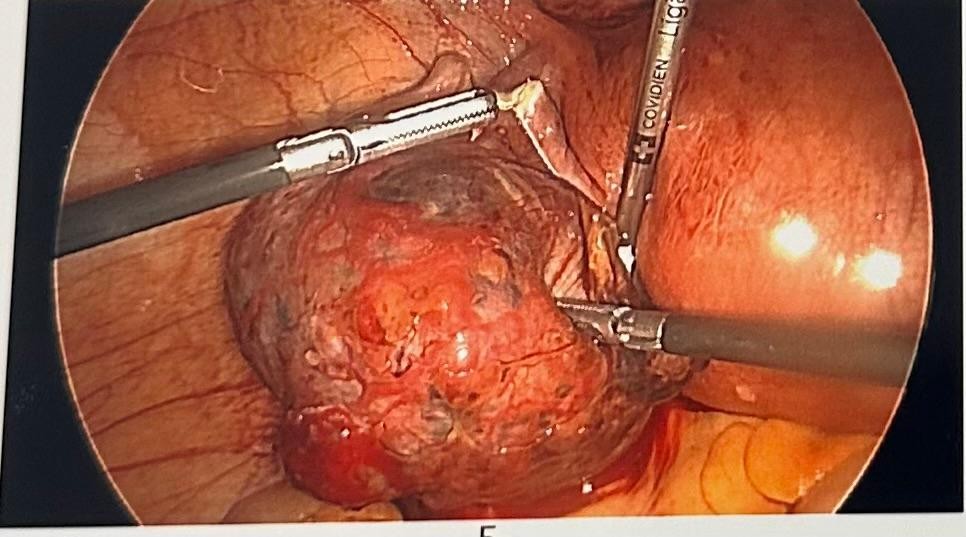

Her abdomen was mildly tender on examination with voluntary guarding. A transvaginal Ultrasound showed a viable intrauterine pregnancy at 12+4 weeks and another viable left tubal ectopic pregnancy of 11 weeks + 6 days gestation. She underwent laparoscopic surgery where a small amount of bleeding was seen in the abdomen, and an ectopic mass in the left adnexa. This mass was removed safely using Ligasure. The procedure was uncomplicated with 100mls of blood loss. She had a bedside USS post-op op which confirmed a viable intrauterinepregnancy.

Figure 3

The laparoscopic approach has been proven to be an effective and safe option in managing early ectopic pregnancy. Surgical management by laparoscopic salpingectomy in a tubal ectopic pregnancy is generally a safe procedure with no increase in fetal loss rate in the IUP. Surgical management has the advantage of complete removal of the ectopic pregnancy mass. However, the outcomes and the complexity of the surgery can vary depending on the location of the ectopic component of the ectopic pregnancy. [13]

In this case, the decision was to proceed with laparoscopy, with the possibility of laparotomy. The decision was appropriate given the patient presentation; was in pain, had viable heterotopic pregnancy, thus laparcoscopic salpingectomy was safe and appropriate.